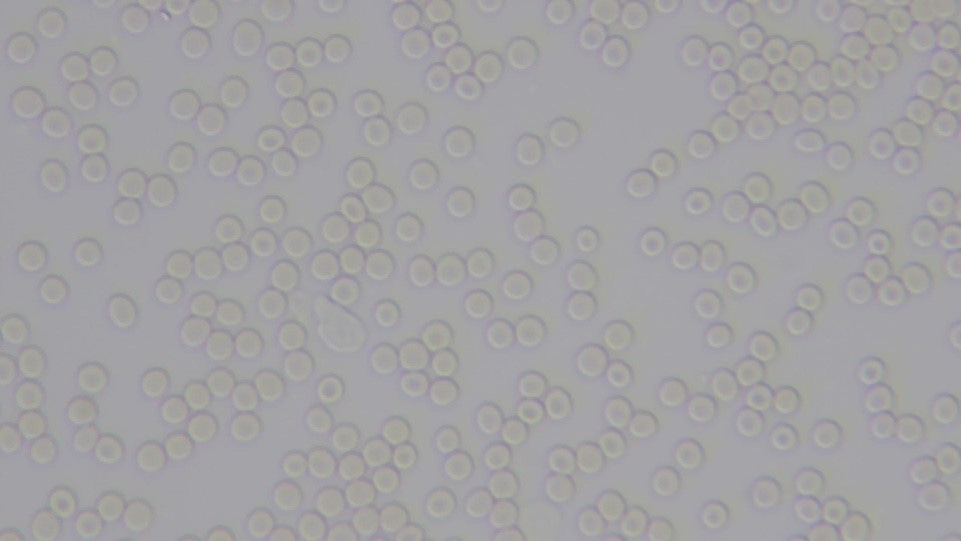

Picture #2 - My Blood AFTER the Sound Treatment - Sample #2.

See all of the nicely-spaced red blood cells? Somehow, someway, the sound treatment seemed to have fixed my blood’s electrical problems. I was impressed!

When I looked at the picture more intently, I realized something was wrong. The blood in the second sample looked too light. I picked up the slide with the first sample on it, so I could compare it to the one I was looking at now. The blood on the first slide was still quite red, in spite of being two hours old. Go back up to Picture #1. Do you notice the difference in color?

Paler red blood cells have less Hemoglobin in them than redder ones do. Hemoglobin helps red blood cells carry oxygen around the body. To produce it, the body needs Iron. My much greyer blood, post sound treatment, lacked iron.